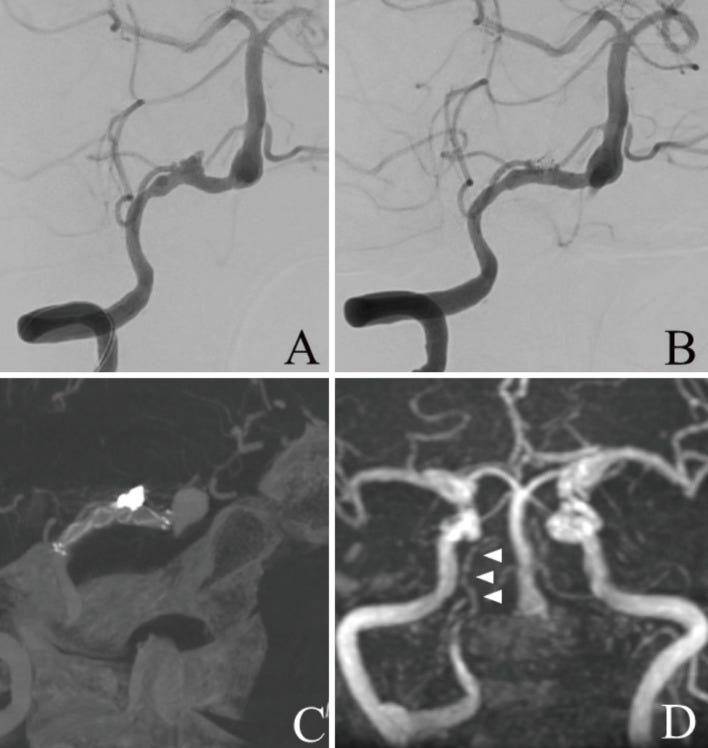

(A) Magnetic resonance angiography (MRA) performed 10 years previously shows normal right vertebral artery (VA). (B) MRA performed 3 weeks before the vaccination shows dilatation of the right VA (arrowhead). (C) Fluid-attenuated inversion recovery magnetic resonance imaging (MRI) performed on the same day shows no intracranial hemorrhage. (D) Head computed tomography (CT) performed 1 day after the vaccination shows diffuse subarachnoid hemorrhage. (E) Chest CT performed on the same day shows bilateral pulmonary effusion. (F) Three-dimensional CT angiography (3DCTA) performed on the same day shows dissecting aneurysm in the right VA (arrowhead). The right posterior inferior cerebellar artery (PICA) originated from the extradural segment of the VA (arrow).

(A) Frontal view of the right vertebral artery angiography (VAG) before internal trapping shows dissecting aneurysm in the right VA. (B) Frontal view of the right VAG after internal trapping reveals that the dissecting lesion was occluded just distal to the origin of the right posterior inferior cerebellar artery (PICA). (C) Frontal view of the left VAG after internal trapping also reveals that the dissecting lesion was occluded. (D) Postoperative magnetic resonance angiography (MRA) performed 2 weeks after treatment reveals that the dissecting lesion of the right VA was not visualized.